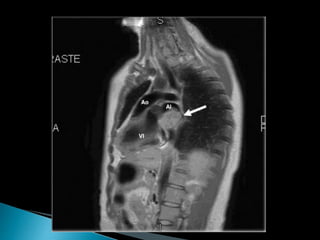

● RMN

 Mejor caracterización tisular

 Poca resolución temporal

• Resonancia Magnética

•Hiperintensos en T2

•Áreas calcificadas: hipointensas

•Realce heterogéneo con contraste